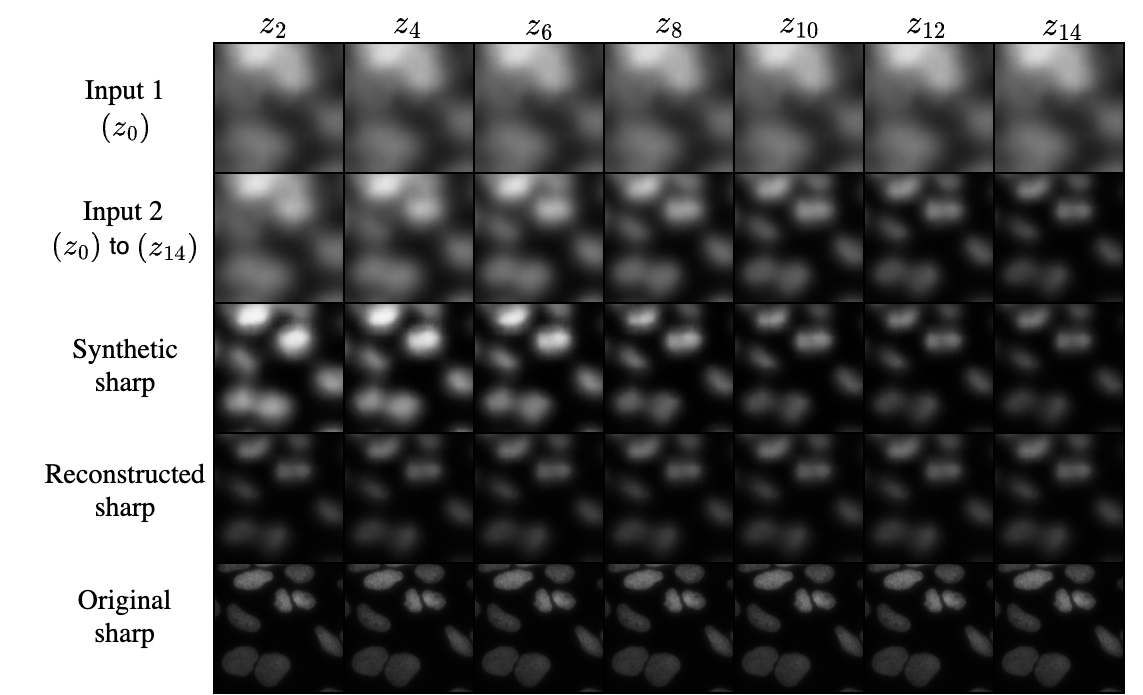

We report the results of the quality of the deblurred images in Table 1. We show examples of deblurred images of a slide in w1 set by the baseline and regularized models in Fig. 3c. Using two blurry images, we can generate a sharper image. For the w1 set, the indirectly regularized autoencoder outperforms the baseline model when we compare the deblurred images with the reconstructed sharp images (see PSNRdextrdsuperscriptsubscriptPSNR𝑑𝑒𝑥𝑡subscript𝑟𝑑\mathrm{PSNR}_{d}^{extr_{d}}). For the w2 set, direct regularization performs the best. We observe that there is a trade-off between the desired geometric property and the image quality when applying direct regularization. With a better regularized latent space, the reconstructed image fidelity decreases slightly, while allowing to reconstruct and generate new images with different levels of blur using linear interpolation and extrapolation of the latent representations, respectively. To account for the clustering induced by the direct regularization, we also generate synthetic sharp images with an adjusted value for α𝛼\alpha (α=0.05𝛼0.05\alpha=0.05). We notice that this set of images shows slightly more sharpness compared to those using α=0.125𝛼0.125\alpha=0.125. This indicates that the levels of blur are indeed encoded along the linear direction in the latent space.

Refer to caption

Figure 4: Effect of the blur level in the input images on the synthetic sharp image, when the optimal interpolation parameter α𝛼\alpha is known, using the indirectly-regularized model.

With our regularized model, even when the sharp image is generated from two images with high levels of blur, a considerable level of detail is recovered. Fig. 4 shows how the blur level of input images affects the deblurring process. We fix one image at z-stack 0 and vary the other one from z-stack 2 to z-stack 14. These results are in line with those from a similar study [9], where the level of detail recovered in the deblurred images decreases with an increase in the focal plane at which slides are captured.